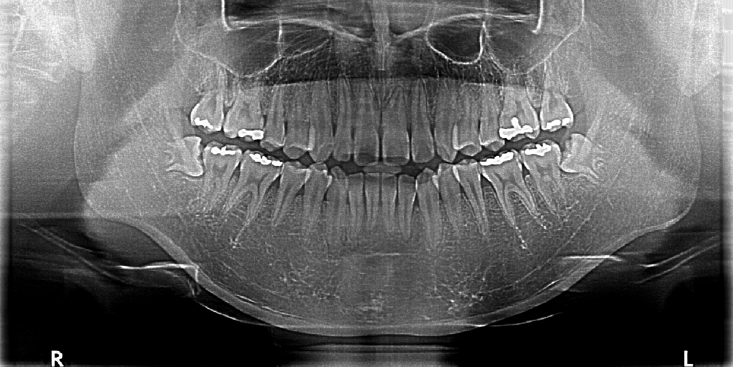

Minocycline-induced discoloration of the alveolar bone: A case report

2025;63(11):346-352. Published online November 30, 2025